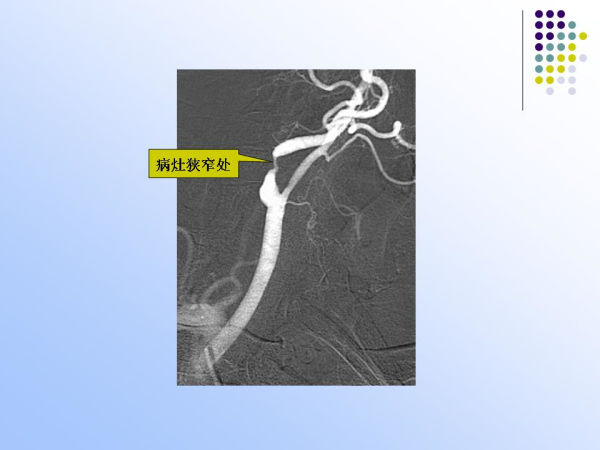

【治疗脑血管病的新技术:血管内介入治疗】—神经内科脑卒中筛查与防治办公室

脑卒中筛查与防治办公室